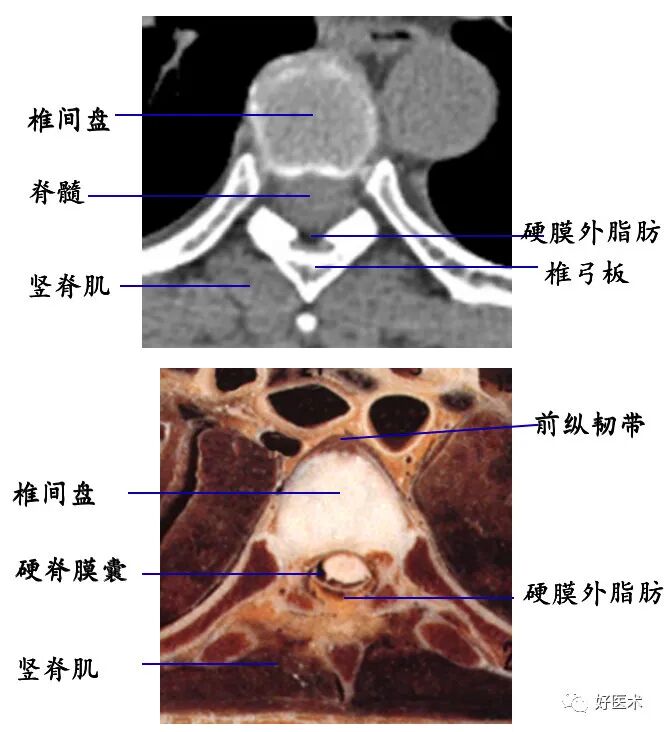

1. 经椎弓根的横断层面:

断面经过的部位:椎弓根

主要特征:椎管为完整性骨环,由椎体、椎弓根和椎弓板构成

3. 经椎间盘的横断层面:

断面经过的部位:椎间盘

主要特征:椎管呈不完整的骨性环,其断开处为椎间孔下部,不同部位椎间孔下部经过的结构不同,颈段主要为脊神经根,胸腰段主要为椎间静脉。

4. 椎管及内容物

硬膜外脂肪:低密度影

硬脊膜囊:呈圆形或椭圆形软组织密度影。CT平扫不能区别硬脊膜囊、脑脊液和脊髓。

椎间盘:呈软组织密度影,CT值为70±5HU,不能区分髓核和纤维环

髓核:T2WI上呈较高信号

纤维环:T1WI和T2WI上均显示为低信号

sharpey纤维:T1WI和T2WI上均显示为低信号

透明软骨板:T1WI和T2WI上均显示为低信号

脊椎韧带:

前、后纵韧带均较薄,CT上不能单独显示。

黄韧带较厚(正常时≤3 mm),位于椎板和关节突的内侧面,密度高于硬脊膜囊和硬膜外脂肪,显示较清晰